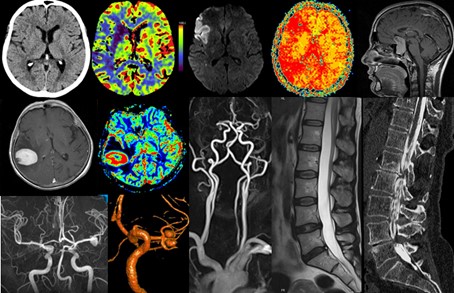

Unser Leistungsspektrum umfasst alle Bereiche der diagnostischen und interventionellen Neuroradiologie. Schwerpunkte sind die multimodale Diagnostik bei zerebrovaskulären Erkrankungen, entzündlichen und neurodegenerativen Erkrankungen, Hirntumoren und Epilepsie und die interventionelle Neuroradiologie mit minimal-invasiver Therapie zerebraler Gefäßmalformationen (Aneurysmen, Fisteln, Angiome), der akuten Schlaganfallbehandlung (Thrombektomie), der Devaskularisation von Tumoren und Blutungen sowie der PTA/Stentimplantationen bei Stenosen der Hirn- und Halsgefäße.

Bildgebende Diagnostik

Die Neuroradiologie am Klinikum Bayreuth ist apparativ sehr gut ausgestattet und bietet für sämtliche diagnostische wie interventionelle Verfahren Geräte der neuesten Bauart.

Hierdurch ermöglichen wir für sämtliche bildgebende Fragestellungen, mit einem besonderen Schwerpunkt in der Neuroradiologie, Bilder und Befunde auf höchstem Niveau.